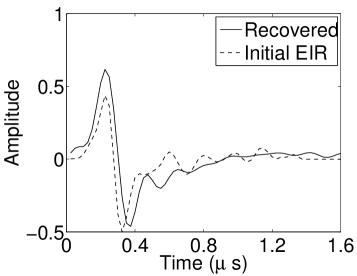

The reconstruction region ( mm2) was represented by pixels with pixel size mm in each dimension. The initial guess of the EIR employed in the VP algorithm was different than the EIR that was assumed when generating the simulated data. This served to simulate a situation in which an experimentally measured EIR contained errors.

Each element in a real-world transducer array possesses its own EIR. In practice, the differences between the EIRs are sometimes neglected and an EIR corresponding to a single element may be used to represent all elements in the array. In some of the studies below, the EIR employed to initialize the VP algorithm (EIR-2 in Figure 1(b)) and the EIR employed to produce the simulated measurements (EIR-1 in Figure 1(b)) were experimentally measured from two different transducer elements in a circular transducer array (see Sec. VI-B). EIR-1 was measured by temporally integrating the PA signal produced by a point source positioned at the focus of the transducer. EIR-2 was measured by use of the method reported in [RNR2011]. In order to investigate the sensitivity of the VP algorithm to the initialization of the EIR, we employed different EIRs obtained by degrading EIR-1 as described later. When solving the sub-problem in Line-2 of Algorithm 1, was initialized as the zero vector. Algorithm 1 was terminated after 500 iterations, since it was observed that the changes in the reconstructed images with more iterations were negligible. When implemented by use of a single core of an Intel Xeon E5-2640 CPU, each iteration required approximately 7s to complete.

Figure 2(a) shows the image reconstructed by use of the conventional iterative method that utilized a system matrix based on EIR-2. Different values of the regularization parameter from the interval were considered. The reconstructed image with the value of that minimized the RMSE was chosen to represent the best performance of the conventional iterative method. Figure 2(a) and the profile in Figure 2(c) demonstrate that the use of an inaccurate EIR can result in strong artifacts and distortions in images reconstructed by use of the conventional methods.

When the VP algorithm was applied, different values of the regularization parameter from the interval and from the interval were considered. The image that minimized the RMSE was chosen and displayed in Figure 2(b). As revealed by this image and the profiles in 2(c), the VP algorithm yielded an image with fewer artifacts and distortions, and image fidelity was improved as reflected by the reduced RMSE.

As shown in Figure 6, when the error in the EIR was small (e.g., as with the EIR in Figure 6(a)), images were reconstructed with high accuracy using the VP algorithm. When the perturbations in the EIR were stronger (e.g, as in Figure 6(c)), artifacts and distortions in the reconstructed images were still significantly reduced by use of the VP algorithm; however, larger values of the regularization parameters had to be applied. When as in the initial EIR in Figure 6(e), no improvement was observed in the image reconstructed by use of the VP algorithm.

Figure 7(a) reveals that use of the inaccurate EIR in the conventional iterative method created strong artifacts and distortions. Figures 7(b) confirms that the artifacts and distortions were significantly mitigated when the VP method was employed. Image profiles for both cases are shown in Figures 7(c). The overall accuracy of the recovered EIR, shown in Figure 7(d) and 7(e), was improved, but it contained spurious oscillations.